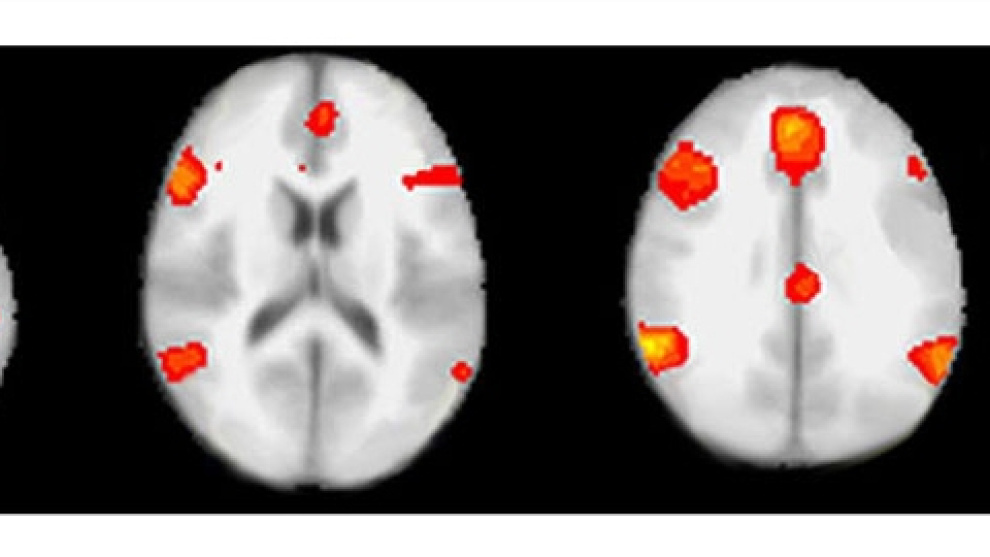

Aunque tampoco es infalible, el análisis de la actividad cerebral indica mucho mejor que el polígrafo cuando una persona miente, según el primer estudio comparativo de los dos métodos. Los expertos en resonancia magnética funcional (fMRI), la técnica utilizada para “ver” la actividad de las neuronas en las distintas zonas cerebrales, fueron un 24% más eficaces en la detección de mentiras que los profesionales del polígrafo, sobre datos recogidos de los mismos sujetos sometidos a la misma prueba. El estudio ha sido financiado en parte por el Ejército de Estados Unidos.

“Las medidas que hace el polígrafo reducen la compleja actividad del sistema nervioso periférico a unos pocos parámetros, mientras que el escáner ve miles de conjuntos neuronales con mayor resolución tanto en el espacio como en el tiempo”, explica Daniel D. Langleben, director del estudio comparativo. “Aunque ninguna de estas actividades se deba solo las mentiras, hemos encontrado, como pensábamos, que la actividad cerebral es un marcador más específico de las mentiras”. Se ha demostrado que cuando alguien miente se “encienden” en el escáner áreas del cerebro relacionadas con la toma de decisiones, lo que permite una eficacia del 90% en la detección de mentiras, mientras que el índice de eficacia del polígrafo no se ha conseguido establecer con seguridad, lo que hace que no se acepte habitualmente a efectos legales, indican los investigadores, de la Universidad de Pensilvania.

El factor clave de ambos estudios es el diseño de los experimentos. En el primero han participado 28 personas, que han realizado una prueba que es estándar en el polígrafo, pero esta vez han sido sometidos a ambos métodos de análisis. Las dos herramientas han fallado en algunos casos, pero el escáner ha resultado ser en conjunto un 24% más eficaz en la detección de mentiras. Además, en los 17 casos en los que el polígrafo y el escáner coincidieron en el diagnóstico, este resultó ser correcto. Como el experimento no estaba diseñado para evaluar el uso combinado de escáner y polígrafo, no se pueden sacar conclusiones prácticas sobre este aspecto. “No sabemos todavía si la resonancia se convertirá en una herramienta forense, pero estos datos justifican seguir investigando sus posibilidades”, concluye Langleben.